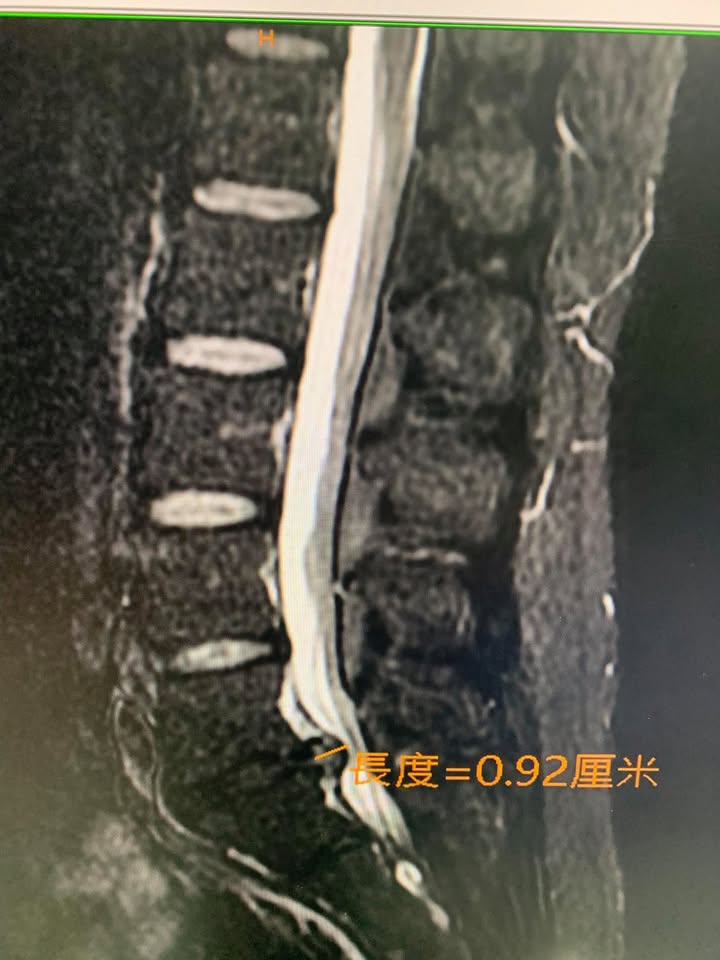

😂高強壯大的駱先生抱怨腰痛連小腿外側跟腳踝,痛了快半年,最近一個月嚴重惡化,走一兩百公尺就需要坐下來休息,右腳踩步明顯跛行,直腿抬高測陽性反應,加強測試會痛一下,墊腳有一點無力,經台北醫學院核磁共振mri證實L5S1中央型巨大突出,來診時已痛苦不堪,所有的椎間盤理學檢查幾乎都是陽性反應,因為患者畏懼開刀所以嘗試脊椎中醫微創療法,治療五次幾乎改善九成以上,非常開心替針刀醫學療法見證,真心恭喜駱先生,並且囑咐這次治療好之後要認真加強下背核心肌群

✳️診斷

1.椎間盤巨大突出合併神經根卡壓

2.多裂肌萎縮

🔎多裂肌可以看到嗎?

可以的!透過核磁共振與肌肉骨骼超音波都看的到 ,在個案中發現駱先生多裂肌萎縮被脂肪組織白色部分填充